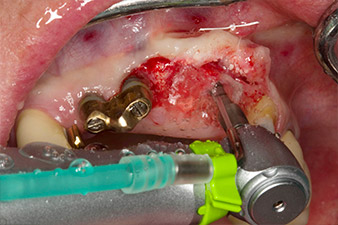

Materiale xenogenico di sostituzione ossea

Fig. 5: Al fine di ottenere la migliore qualità possibile del tessuto periimpianto, è stato eseguito innesto osseo nella sede di impianto con materiale xenogenico di sostituzione ossea e una membrana di collagene, in vista della rigenerazione guidata dell'osso.

Situazione in seguito a impianto

Fig. 6: Situazione in seguito a impianto e innesto: Il ponte vecchio è stato reinserito come ricostruzione temporanea durante la fase di guarigione con una protesi fresata in corrispondenza della posizione di impianto 22. La protesi finale programmata sarà un ponte in ossido di zirconio da 12 nell'impianto di inserimento in corrispondenza della posizione 23.